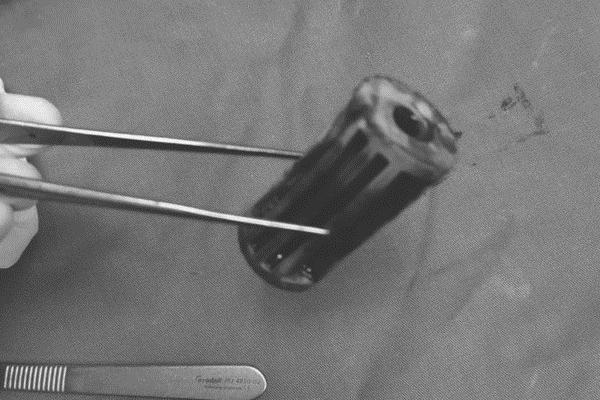

Thanh sắt được lấy ra từ hậu môn của bệnh nhi 6 tuổi. Ảnh BVCC